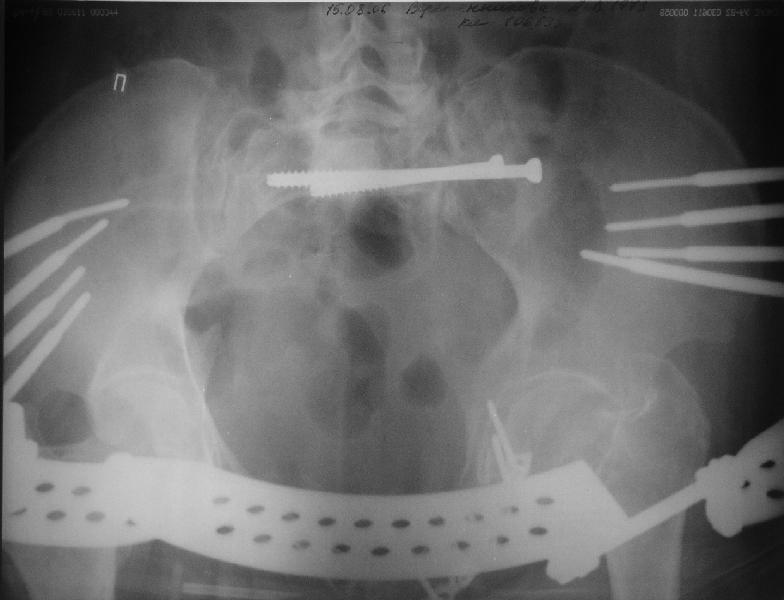

Прооперировали молодую девушку 32 лет спустя 9 мес после травмы. Имелся стойкий болевой синдром, неопороспособность левой н/конечности, моторные и сенсорные нарушения в левой голени и стопе, патологическая подвижность левой половины таза. Первым этапом закрыто в аппарате исправили деформацию ( в течении 2,5 нед). Вторым закрытое введение илиосакральных винтов в крестец (канюллированные 7,2 мм Chm) + туннелизация зоны псевдоартроза спицама Киршнера, реконструкция передних отделов таза, накостный остеосинтез . Аппарат частично демонтирпован, оставлена "передняя рама" После устранения деформации отмечен регресс неврологической симптоматики, уменьшение болевого синдрома. Интересующие вопросы: 1. Прогноз для сращения псевдоартроза крестца. 2. сроки нагрузки весом левой половины таза. Буду очень признателен за ваши мнения по этому поводу.A female 32 y.o. admitted to our unit 9 months after initial injury with pain, inability to bear weight at the left lower limb, sensor and motor disturbances in the left foot and tibia, with mobility of the left hemipelvis.At first closed reduction was performed by an external fixator within 2,5 weeks. After correction her pain decreased and some neurological progress was achieved. Now two iliosacral screws 7,2 mm were inserted, and anterior lesion was fixed by a plate. External fixator was partially unmounted, only anterior frame left in place.Images attached.How would you evaluate chances of healing of the sacrum with the current position?When would you allow weight-bearing of the left leg?THX in advance.

Мне нравится ваша закрытая репозиция девятимесячного ложного сустава, не знаю насчет туннелизации, но шурупы в 7.2 это серёзная конструкция. При стабильной фиксации крестец должен срастись, только я бы держал передний фиксатор до шести недель, костыли, а полную нагрузку разрешить через 12 недель.